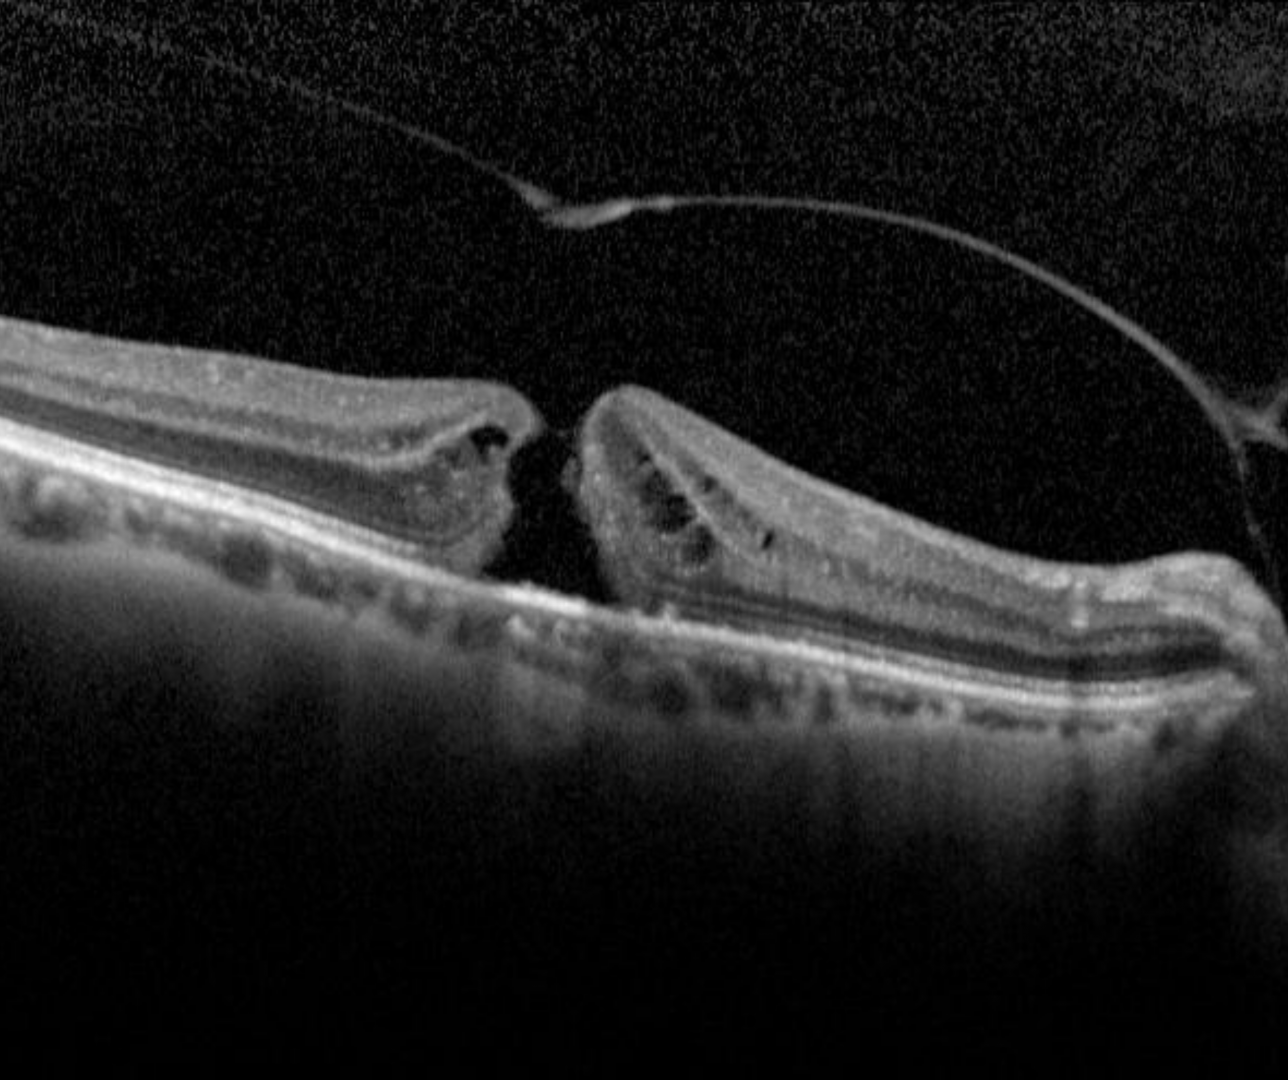

Full thickness macular hole (FTMH) is a full thickness break at the fovea and can be caused by tractional forces from the vitreous, ERM or trauma.

OCT shows loss of all the foveal layers from the internal limiting membrane up to (but not including) the RPE. The edge of the hole is rounded and may contain pseudocysts. The International Vitreomacular Traction Study Classification System for Mitreomacular Adhesion, Traction and Macular Hole developed a classification system for classifying a hole size by OCT measurement of its narrowest aperture.

Small: ≤250µm

Medium: >250µm- ≤400µm

Large>400µm

Case 1: Large FTMH

A 70 year old Asian female with best corrected visual acuity of 6/60 (20/200) - pinhole yielded no improvement.